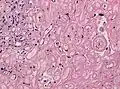

Менинготелиоматозная менингиома состоит из мозаикоподобно расположенных клеток с овальным или округлым ядром, которые содержат умеренное количество хроматина. Строма опухоли представлена немногочисленными сосудами и тонкими тяжами соединительной ткани, которые окаймляют клеточные поля. Характерны концентрические структуры из наслаивающихся одна на другую уплощённых опухолевых клеток. Центр новообразования часто обызвествлён[3].

Фиброзная менингиома состоит из фибробластоподобных клеток, которые располагаются параллельно друг другу и складываются в переплетающиеся между собой пучки, содержащие соединительнотканные волокна. Ядра вытянутые. Могут встречаться концентрические структуры и псаммомные тельца[3].

Переходная менингиома включает элементы менинготелиоматозной и фиброзной менингиом[3].

Псаммоматозная менингиома содержит большое количество псаммомных телец[3].

Ангиоматозная менингиома обильно васкуляризирована, содержит большое количество кровеносных сосудов[7].

Микрокистозная менингиома содержит большое количество микрокист, окружённых опухолевыми клетками звёздчатой формы[8].

Секреторная менингиома является редким гистологическим вариантом данного новообразования. Для неё характерна секреция веществ, которые формируют гиалиновые включения[9].

Менингиомы с обилием лимфоцитов по определению содержат большое количество включений лимфоцитарных масс.

Для метапластических менингиом характерна метаплазия (трансформирование) менинготелиальных клеток в клетки другого типа (к примеру, адипоциты)[10].